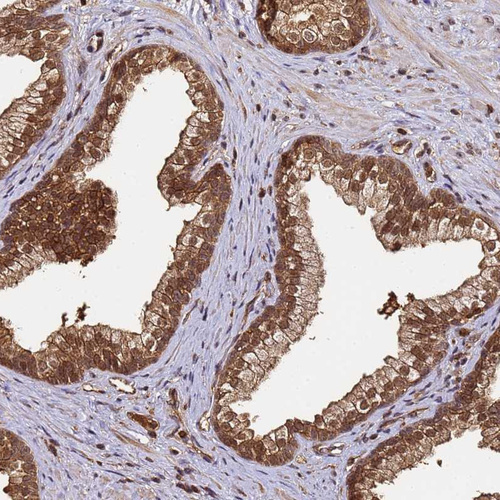

Immunohistochemical staining of human nasopharynx shows strong nuclear and cytoplasmic positivity in respiratory epithelial cells.